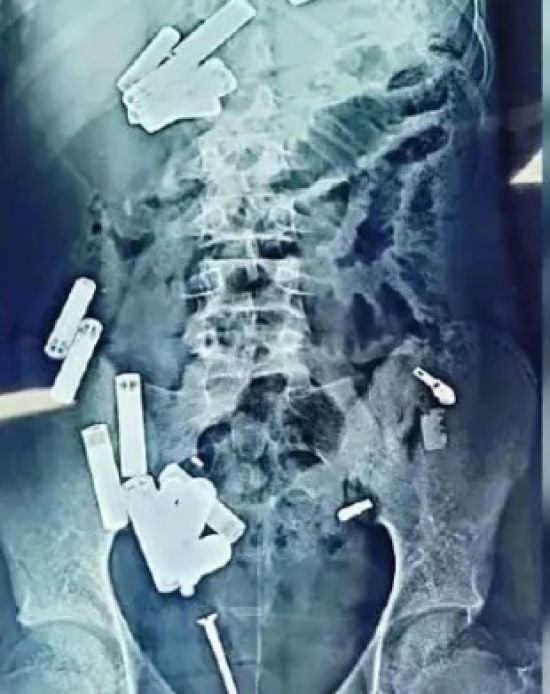

15-річний хлопчик помер після того, як хірурги дістали з його тіла 56 металевих предметів – фотоВід / 06.11.2024 Він проковтнув батарейки, ланцюжки, уламки бритви та гвинти.